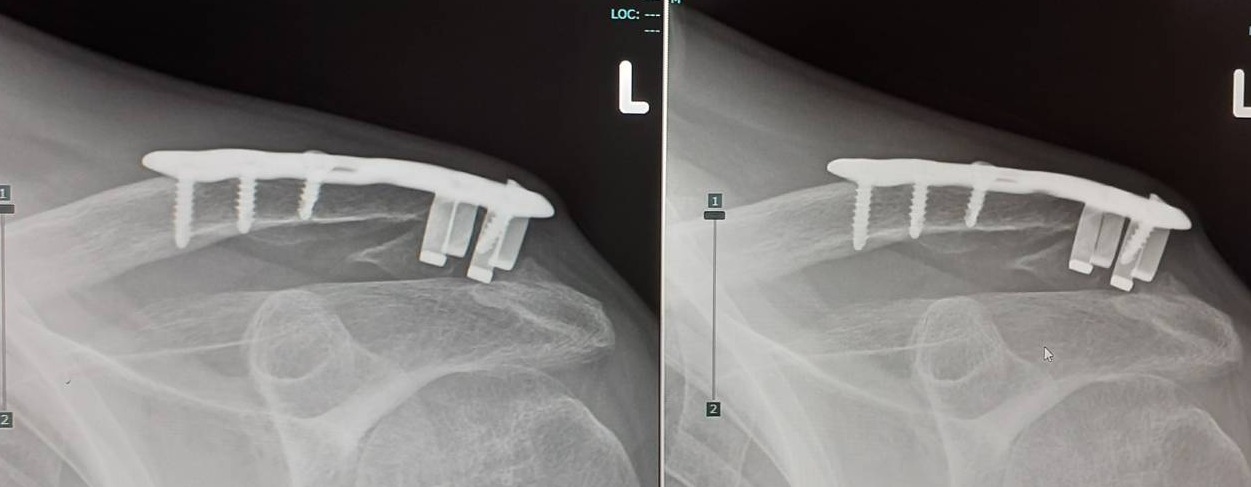

この記事の続き。月イチペースでレントゲン撮って経過観察はしていた。最初の2ヶ月ほどは順調だったがその後の治癒が進まない。9月になって主治医さんと色々話してるうちにわかった。「動かさなかったこと」が原因で骨が接合しないらしい。普通、これって逆を考える。早く治るようにと思って3ヶ月左肘を体にくっつけて生活していた。そんな状態で動かさなかったらそれが原因で治りが遅くなるらしい。本塁突入のサードコーチャーみたいにぐるぐる回せと言われた。そんなの聞いとらんしwってことで、プレート除去手術をする。11/29(金)朝から入院して即手術。11/30(土)昼に退院して、ワンコの散歩行って教室に来て中3授業の予定。プレート埋め込みよりも負担が少ないらしく、コレでいけるでしょ!Cちゃん先生、金曜日の教室運営お願いしま~す。金具の下の骨の裂け目の隙間がある。この部分が繋がっていないらしい。CTで角度変えて見るとほかの部分は繋がってるので大丈夫だろうってことらしい。